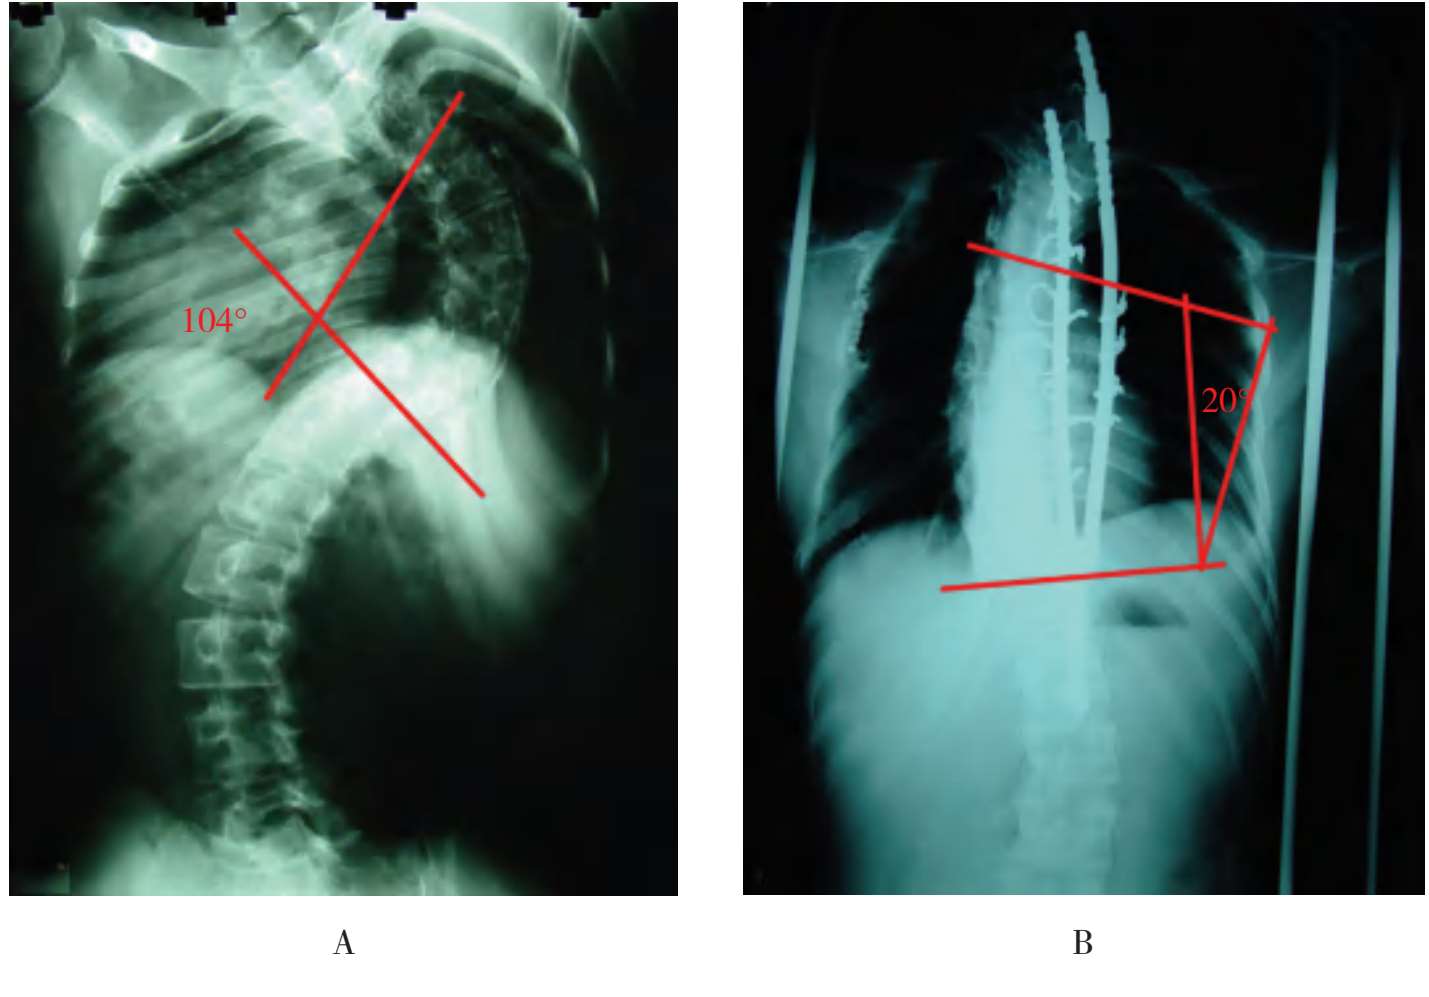

A.术前X线片示Cobb’s角104°;B.经颅盆牵引加弹性分叉生长棒矫正术后Cobb’s角变为20°;C、D.术前人体外形;E、F.颅盆牵引后人体外形;G.术后石膏背心外固定,正面观;H.背面观

图3-11 患者女,16岁,特发性重度脊柱后侧凸伴胸廓塌陷畸形